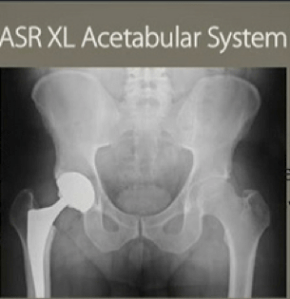

Three years before Johnson & Johnson’s DePuy unit recalled its chromium and cobalt hip implants, company marketers feared the backlash over metal ion debris in patients, a jury in Los Angeles was told.

A DePuy marketing executive, Randall Kilburn, testified today in California state court at the first of 10,000 lawsuits to go to trial over the ASR hips, which J&J withdrew in August 2010 when their failure rate reached 12 percent. Kilburn was asked about a meeting in July 2007 in Chicago, where the marketing team discussed several hip devices.

Jurors are weighing the lawsuit of Loren Kransky, 65, who claims the ASR hip was defectively designed and the company failed to warn of risks. Kransky’s lawsuit and many others claim that the shallow design of the hip cup, in which a metal ball sitting atop the femur rotates, led to the shedding of metal ions in surrounding tissue and bloodstream.

That device advanced metal-on-metal designs of the 1960s and 1970s that had fallen out of favor as metal-on-polyethylene grew popular. DePuy began selling a similar device, the ASR Hip Resurfacing System, outside the U.S. in 2003. Both devices used an alloy of cobalt and chromium.